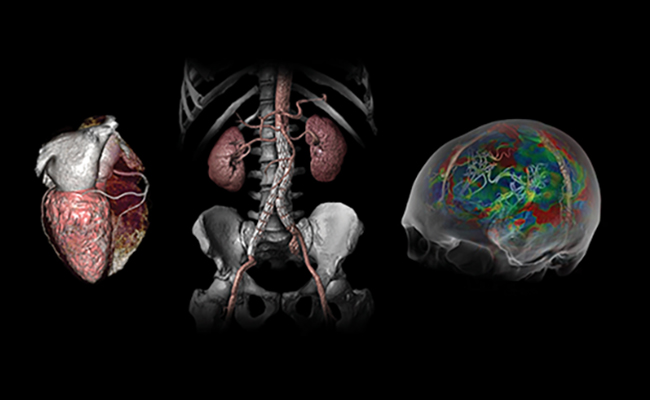

КАРДІОЛОГІЧНІ ПАКЕТИ

НЕВРОЛОГІЧНІ ПАКЕТИ